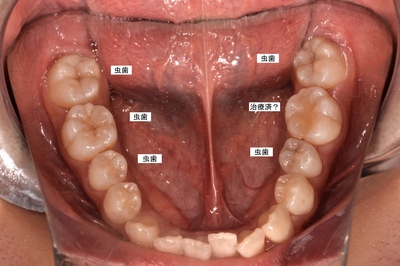

術前

最近他院において治療行ったそうだが、充填部位、向かって右側奥から2番めの歯牙のかみ合わせ悪く、表面がざらつく、また、矯正治療に対しての不満から来院。

他の奥歯は初期の虫歯と言われ、今は治療する必要なしと言われたそうだが、、、、、、それならフォローは?

実際は相当進行しており、何本かは神経処置必要となるギリギリの線まで進行。

明らかな見落とし、お粗末な診断とスキル。

この患者さんはまだ中学生である。